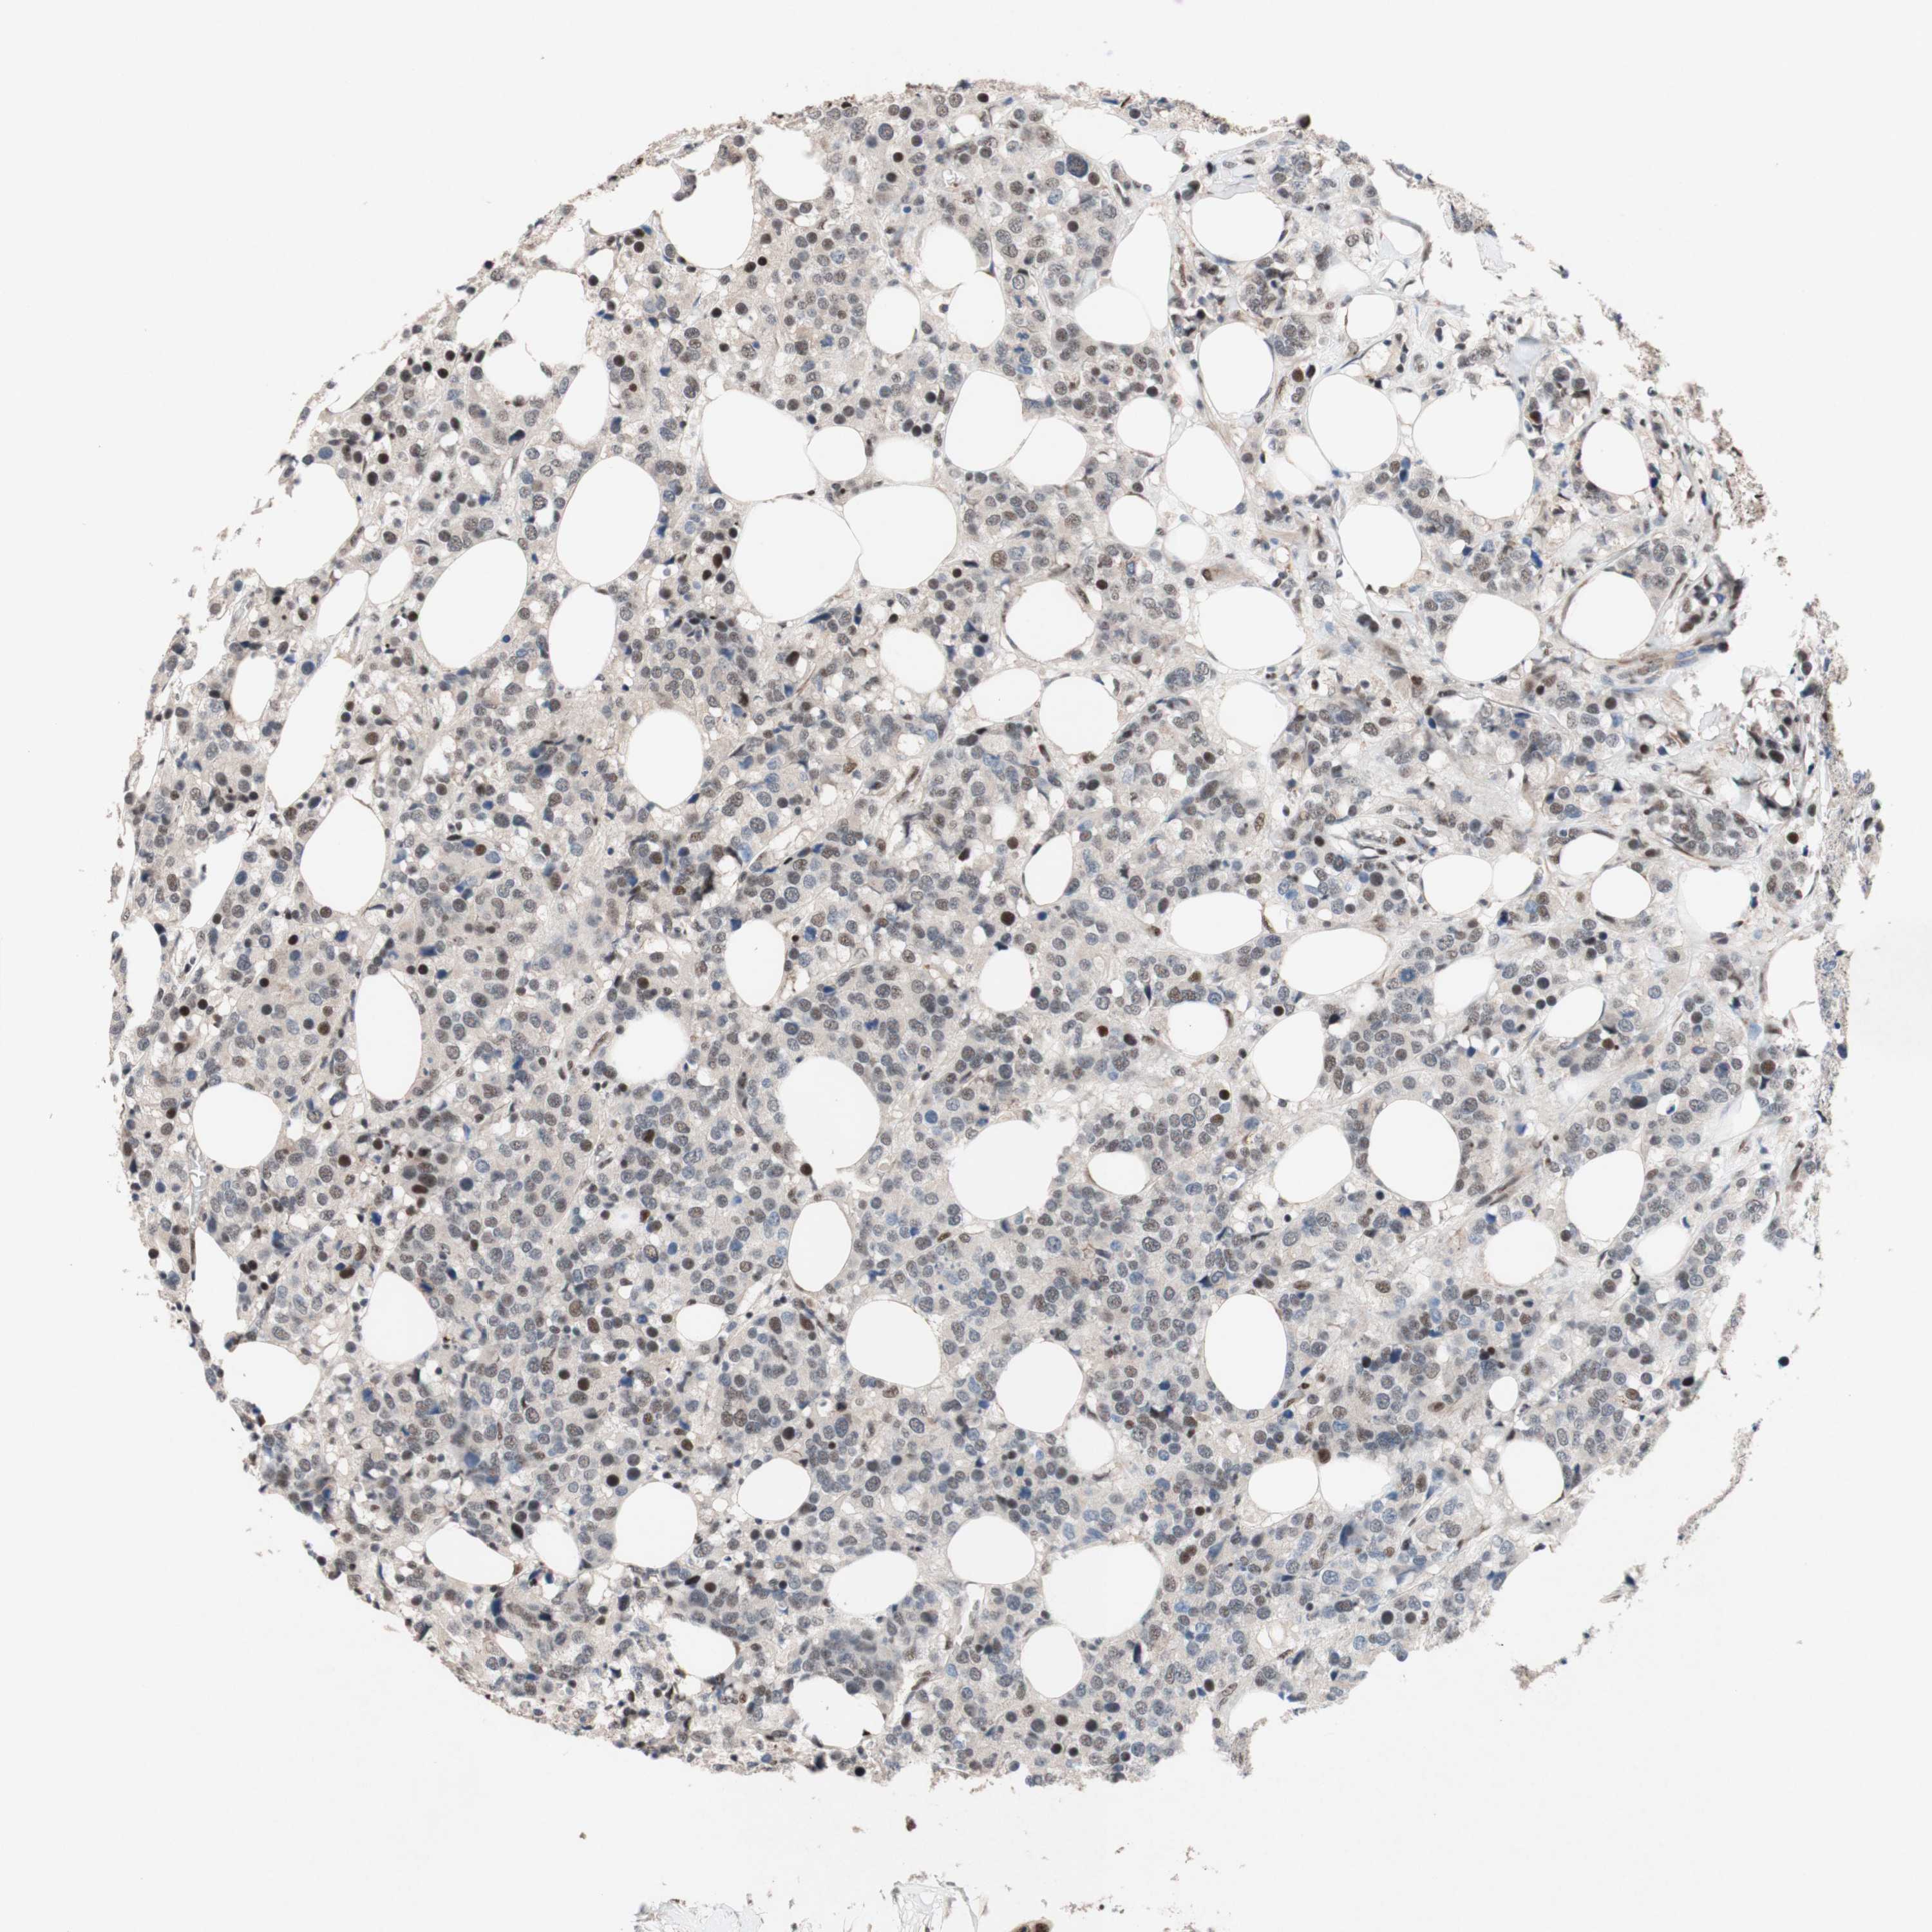

TLE1

CANCER BREAST CANCER Show tissue menu

BRCA TCGA BRCA VALIDATION PROTEIN EXPRESSION